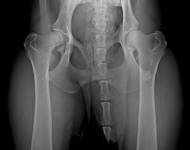

MVDr. Meloun: Lumbosakrální přechodový obratel